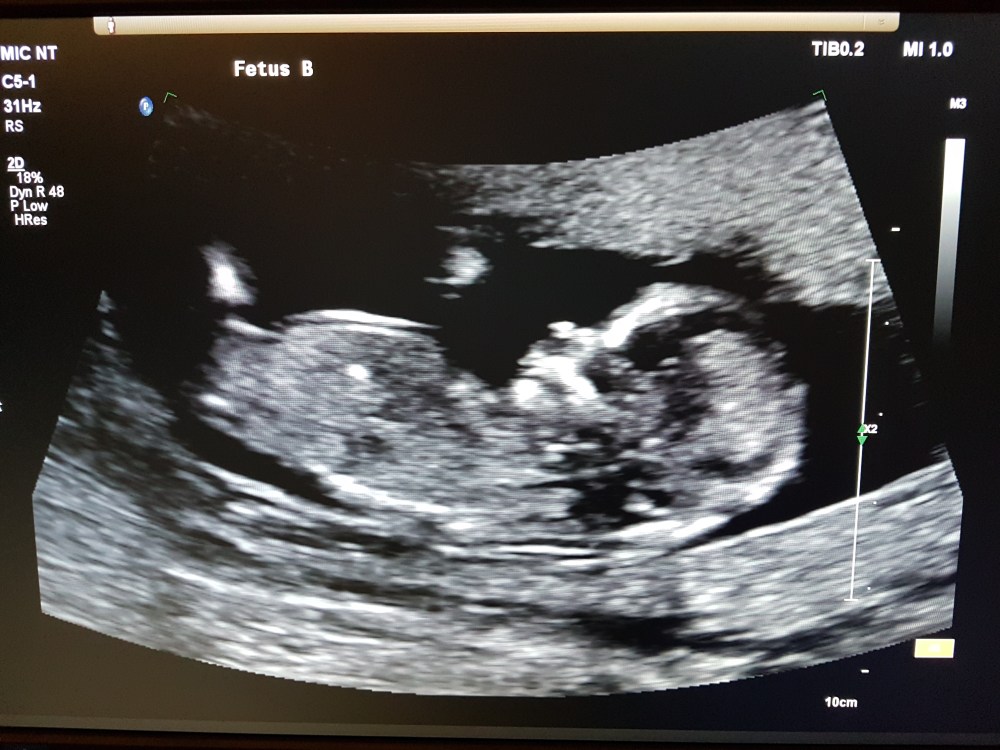

We had our 12 week ultrasound two days ago. It was unbelievable to see our children wiggling and dancing, and being. The Electrician and I have been calling our twins “The Sprouts” for a while, and as of now, they have slightly more elaborate names. I don’t want to always refer to them only as our twins, to tie them together by default because they are going to be born on the same day. These beloved babies will be two separate, distinct people, and I think it’s important to honour that.

And our second beautiful baby, Broccoli Sprout. I was hoping to call this one Brussels Sprout, but The Electrician could not stomach nicknaming our baby after the food he detests above all others.

How incredible are those little faces?